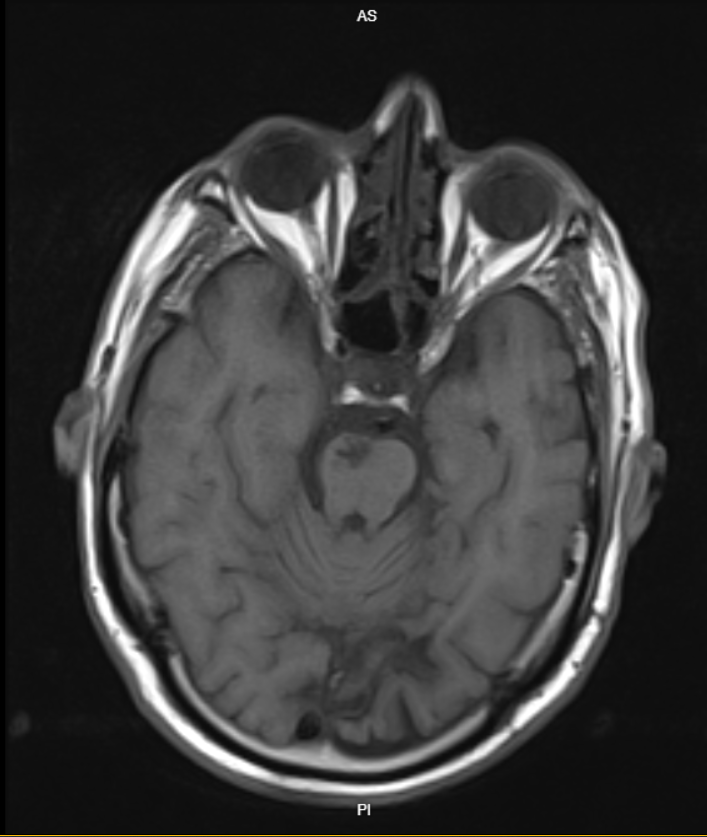

MSE: مختلبیمار آقای ۶۲ ساله MR با شکایت تشدید ضعف اندام تحتانی و اختلال تکلم و اختلال در Horizontal gaze چشم راست به این مرکز مراجعه کرده است . فورس اندام های فوقانی 5/5 و فورس اندام های تحتانی 4/5 است ، بیمار در چشم راست اختلال در adduction حین حرکت هر دو چشم دارد اما در convergence مشکلی نداشت .

MRI:

T1

(تصویر مربوط به این مراجعه نیست) Other: